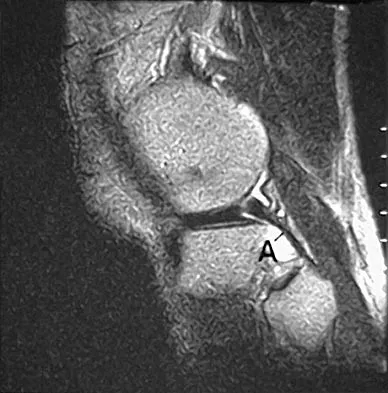

A 16-year-old boy sustains a twisting injury to the left knee while wrestling. MRI scans are shown in Figures 22a through 22c. What is the most likely diagnosis?

Explanation

The primary function of structure "A" in Figure 29 is to limit

Explanation